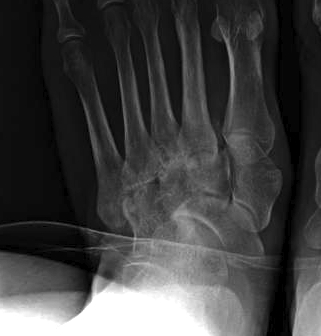

Planovalgus secondary to midfoot OA

Planovalgus secondary to Lis franc